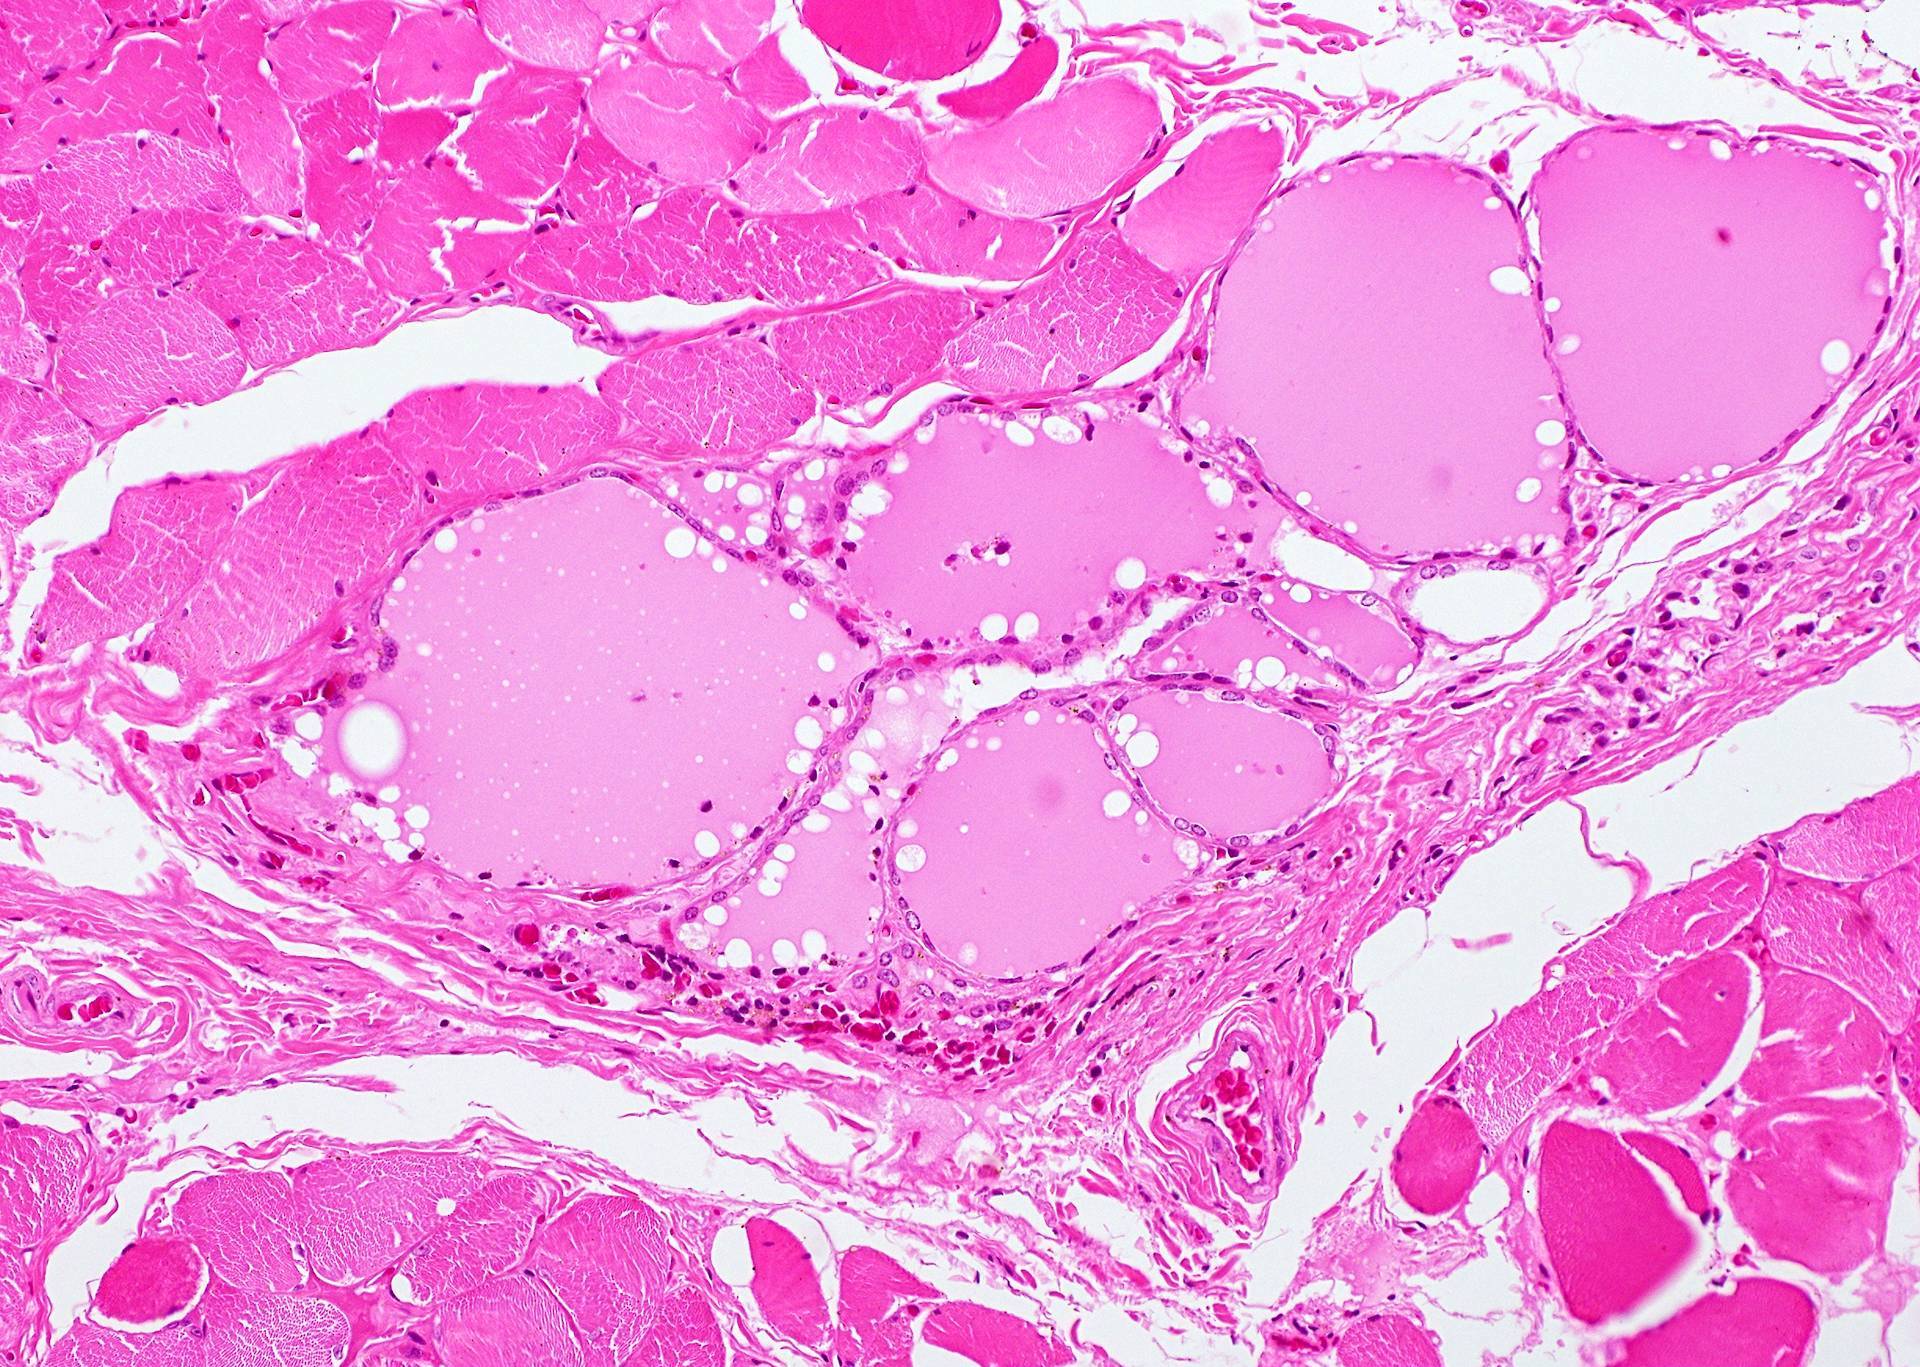

Microscopic (histologic) description

- Type of epithelial lining varies by site, and combinations of the types below can be seen in a single cyst (Head Neck Pathol 2013;7:50):

- Ciliated pseudostratified columnar (respiratory) epithelium in lower neck, perhaps due to its close proximity to upper respiratory tract

- Nonkeratinizing squamous epithelium in higher neck (near tongue and foramen cecum), also can be of metaplastic origin in inflammatory settings

- Stratified cuboidal epithelium at level of hyoid bone

- Very often the cyst is denuded of epithelium, at least focally, which reflects epithelial damage by inflammation

- Secondary inflammation is common, especially in sinus tract (J Pediatr Surg 1984;19:506):

- Intense lymphocytic infiltration, rarely arranged into lymphoid follicles

- Admixture of neutrophils (if the cyst is infected)

- Granulation tissue and fibrosis

- Thyroid follicles in the cyst / duct wall:

- Found in 30% - 60%, with higher yield on serial sections

- More common in infra- versus suprahyoid remnants, on the right paramedian side (Ann Otol Rhinol Laryngol 2000;109:1135)

- Seen in small irregular groups

- Thyroid epithelium may be normal or rarely hyperplastic or neoplastic

- Thyroid tissue often hidden by inflammation (Laryngoscope 2001;111:1002)

- Absence of thyroid tissue does not exclude the diagnosis of TGD cyst

- Mucous salivary-type glands can be found in the cyst wall, frequently in lingual and suprahyoid locations (Ann Otol Rhinol Laryngol 1996;105:996)

Microscopic (histologic) images

Contributed by Andrey Bychkov, M.D., Ph.D., Mark R. Wick, M.D. and AFIP